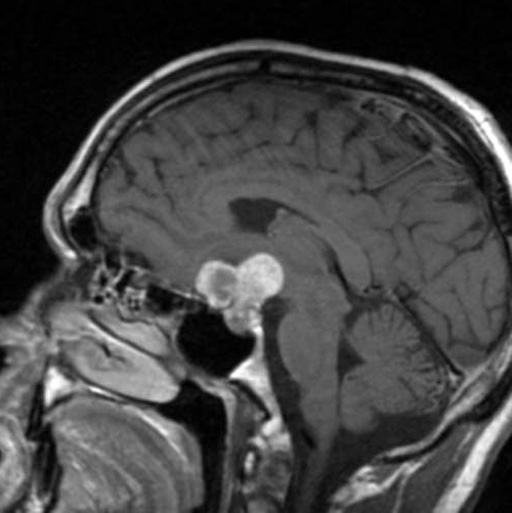

颅咽管瘤 是一种少见的中枢神经系统(CNS)良性肿瘤,被认为是由脑垂体附近的Rathkes囊残余形成。它们占全部原发性中枢神经系统肿瘤的不到1%,但却是儿童...

颅咽管瘤是一种来源于胚胎残余组织的良性肿瘤,颅咽管瘤约占儿童全部脑瘤的6%。任何年龄的人都有可能被诊断为颅咽管瘤,但在5到14岁之间较容易被诊...

如果肿瘤很大,会导致垂体附近的其他神经或动脉受压,是将眼睛与大脑连接的视神经。颅咽管瘤本身不是垂体瘤,而是在垂体腺附近及其上方,在将眼睛...